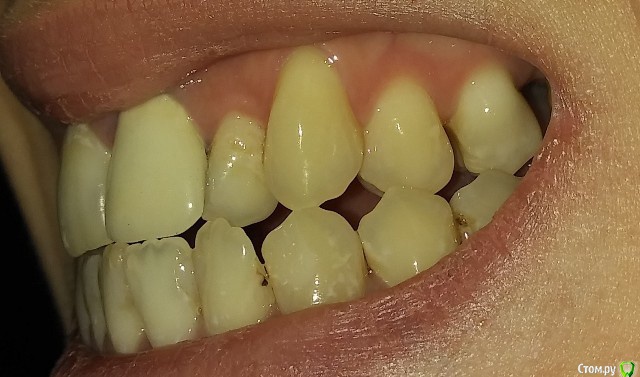

Есть рецессии на нижних зубах и на верхнем клыке слева и резорбция. Ортодонты говорят, что это последствия неправильного прикуса, травмирующего смыкания и с брекетами все стабилизируется, но из-за движения зубов может и усугубиться, как повезет. Вестибулопластику никто не предлагал, а один вообще сказал, что в моем случае она бесполезна. У хирурга-парадонтолога другое мнение: нужно сделать сначала операцию на нижних зубах (углубить преддверие, устранить тяжи и положить какой-то там замещающий материал), а потом поставить брекеты, иначе без операции брекеты спровоцируют еще большее оголение и рецессии станут просто огромными.  А после брекетов уже закрывать, если нужно, рецессии.  Прошу поделиться вашим мнением? В чем причина рецессий и резорбции? Поможет ли в моем случае вестибулопластика?